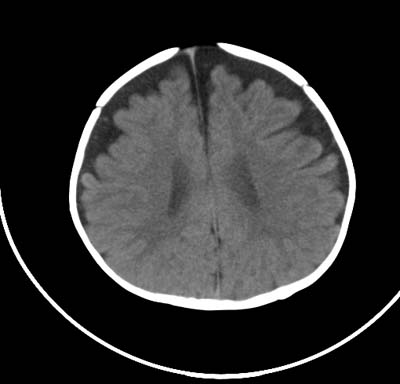

以下是引用影象小泰斗在2008-6-30 15:57:00的发言:[br]双侧额、颞部蛛网膜下腔增宽,纵裂加深, 支持外部性脑积水![br] 双侧基底节点状钙化!

以下是引用jiangjing在2008-6-30 17:19:00的发言:[br]双侧额、颞部蛛网膜下腔增宽,纵裂加深, 支持外部性脑积水![br] 双侧基底节点状钙化![宫内感染形成可能]